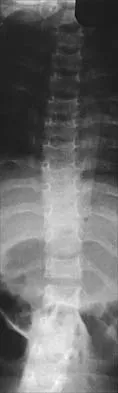

Figures 9a and 9b show the spinal radiographs of a 3-year-old child with short limb dwarfism. The lateral radiograph is obtained with maximal lumbar extension. Management should consist of

Explanation

The patient has kyphosis in association with achondroplasia. The AP radiograph shows decreased interpedicular distance at the lower lumbar vertebrae, a feature considered to be a distinctive sign of achondroplasia. Most patients with achondroplasia have kyphosis, and this usually resolves spontaneously. When the fixed component is greater than 30 degrees, however, brace treatment is recommended. Spinal fusion is seldom required.